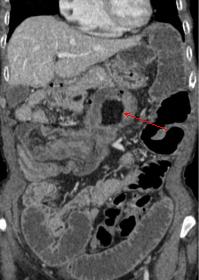

Petit lipome de

l'intestin ( fleche rouge ) . Aspect TDM

arrondie pedicule a hypo-dense endoluminale de

intestin a la region fosse iliaque gauche |